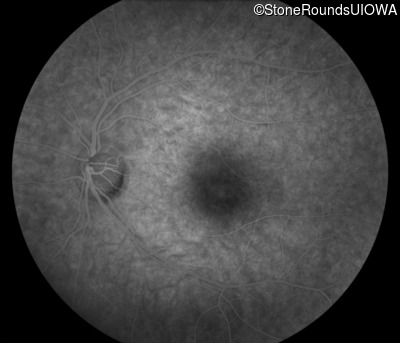

Infrared Fundus Photograph - Right - 20/20 -1

Exemplar